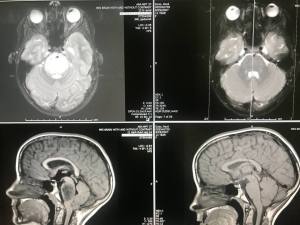

I have read the MRI report stating, “There are no focal areas of abnormal signal, restricted diffusion, or abnormal enhancement within the brain. No mass, hemorrhage or acute infarct is present.” I have seen the before and after MRI images confirming no presence of a tumor. The doctors in Austin, Houston, and Boston have described the report findings as “rare, very rare.” One stated she has never seen this type of results following radiation treatment for DIPG. Doctors have conferred and are confident they did not misdiagnose. The consensus is that the original diagnosis of DIPG was correct, and there is no disputing that the once large, entangled, inoperable tumor is now gone. Lord, I do believe; help my unbelief.

The images on the left are pre-radiation. Those on the right are post-radiation.